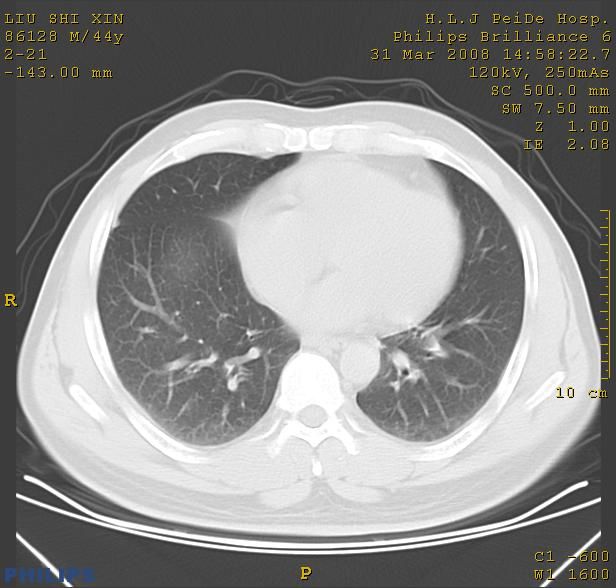

标题: CT13096:请分析胸膜下结节的影像基础是什么 有病理结果 [打印本页]

标题: CT13096:请分析胸膜下结节的影像基础是什么 有病理结果

瘢痕挛缩,胸膜牵拉,血管纠集扭曲,上叶前段支气管显示欠清,周围散在斑片影,以纵隔旁肺癌可能性大。请穿刺检查。

中心型肺癌并阻塞性肺炎、两肺及胸膜多发转移。

结节灶与血管末梢相通象转移灶;小三角状尖部有纤维索是胸膜拉扯征;纵隔旁大片实性影有点状钙化;周围有名显纤维瘢痕征可考虑瘢痕癌

本病例有病理结果是,鳞状上皮癌,胸膜下结节影病现诊断的肿大淋巴结,谢谢大家分析,请问胸膜下结节是肿大淋巴结怎么解释